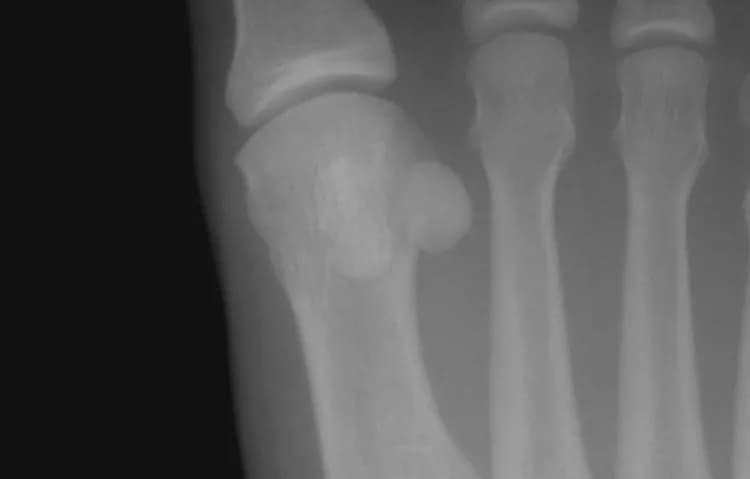

• X-ray of the foot: X-rays use radiation to produce images of the foot. In many individuals, the sesamoid bone close to the center of the foot (the medial sesamoid) has two parts, called bipartite. Given that the edges of the bipartite sesamoid are usually smooth, and the edges of fractured sesamoids are usually jagged, x-rays are very important in assuring a correct diagnosis. A physician may also order an x-ray of the other foot to compare the bone structures